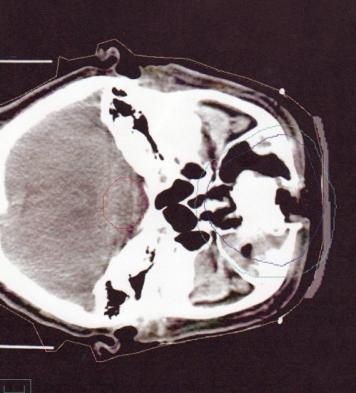

1名55岁的男性患者因泪溢从肿瘤科转到眼科。他患有2型糖尿病10年,目前注射胰岛素治疗,还患有高血压,血压控制良好。他每天吸烟20-40支。1年前因为鼻部浸润性鳞癌而行全鼻切除,术后进行了4周的放疗(见图1)。 放疗总剂量为5250拉德(52.5戈瑞)(每周1312.5拉德/13.12戈瑞, 每次262.5 拉德/2.62 戈瑞)。他的验光师对他进行的糖尿病眼底检查以及2005年4月糖尿病视网膜检查均没有发现糖尿病视网膜病变。没有其他眼部病史。

图1 CT扫描显示鳞癌的区域